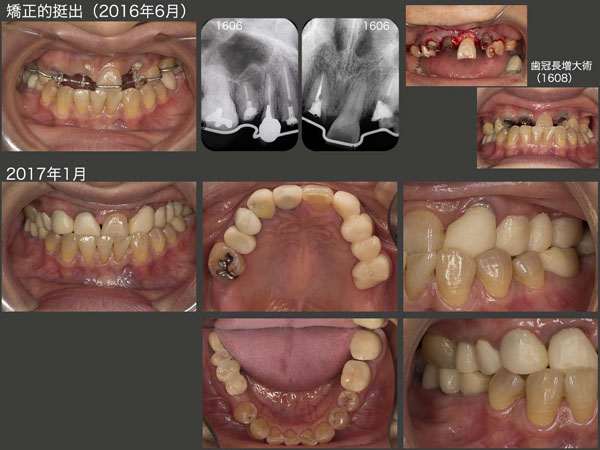

下顎が落ち着いたところで,2016年6月,上顎残根状の右上1,3,5および左上3の矯正的挺出を開始した.なお,左上5,7は保存不可能で抜去した.16年8月,歯冠長延長術を施し,歯肉縁上歯質を確保した.

スライド中,下段は17年1月の状態であるが,すべての基礎治療が終了した.ここから,最終補綴装置の製作に取りかかった.

2018年1月,すべての治療が終了した.左上3はブリッジの支台歯となるには歯の条件が悪いため,根面板を装着し,歯に側方力が加わらないように配慮した.その結果,左上は可撤式ブリッジ(コーヌス義歯)を装着することにした.再植および移植された右下については,連結固定してはじめて機能するが,支台歯の清掃性の向上および将来の変化に配慮し,可撤式の連続冠(コーヌス冠)を装着した.